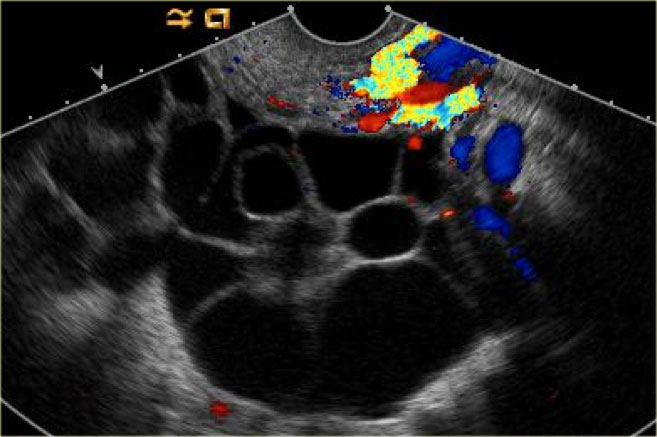

ظاهر کیست تخمدان هموراژیک در سونوگرافی

ظاهر کیست تخمدان هموراژیک بستگی به مرحله تشکیل و مدت زمان تشکیل کیست دارد. کیست می تواند یکی از شکل های زیر را داشته باشد:

1) الگوی رتیکل ریز

این کیست شایع ترین نوع کیست تخمدان هموراژیک است. در این نوع رشته های نازک فیبرین ظاهر شبکه ای ایجاد می کنند که الگوی رتیکل نامیده می شود.

2) ظاهر لخته ای شکل

فرآیند شکل گیری لخته و کیست تخمدان هموراژیک منجر به تشکیل یک لخته مثلثی در بخشی از کیست می شود و مایع سرمی اشباع باقی مانده کیست را پر می کند.

3) سطح سیال باقی مانده در کیست

این نوع نیز شکل دیگر کیست هموراژیک است که در سونوگرافی دیده می شود و مایع باقی مانده درون کیست است. این مایع باقیمانده توسط رسوب یا عناصر ریز در داخل کیست تخمدان هموراژیک تشکیل می شود.

4) پارگی کیست تخمدان هموراژیک

در این حالت ظاهر غیر معمول ایجاد شده، ناشی از پارگی کیست تخمدان هموراژیک است که باعث ایجاد خون در داخل لگن می شود. این حالت به صورت مایع اکوژنیک اطراف کیست و رحم می باشد. اگر خونریزی شدید باشد، ممکن است هموپیریتونوم خون درون کیسه مورینس نیز دیده شود. این شکل پارگی شبیه به بارداری خارج از رحمی می باشد.

5) کیست تخمدان هموراژیک شبیه به یک نئوپلاستیک تخمدانی جامد است!

این نوع نیز شکل دیگری از کیست تخمدان هموراژیک است که مواد اکوژنیک درون کیست را نشان می دهد و معمولا در طول دوره پس از قاعدگی با تشکیل لخته در داخل کیست ظاهر می شود. این شکل کیست شبیه به نئوپلاسم جامد تخمدان است. معمولا در سونوگرافی ها پس از 4 تا 6 هفته تغییرات چشمگیری در کیست هموراژیک دیده می شود.